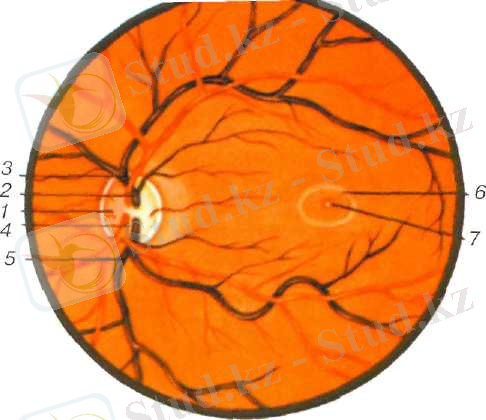

Сурет. 4. Көз түбі. (офтальмоскоппен қарағандағы көрінісі)

/ - көру нерві дискісі; 2 - тор қабықтың орталық венасының жоғарғы тармағы; 3 - тор қабықтың орталық артериясының жоғарғы тармағы; 4 - тор қабықтың орталық артериясының төменгі тармағы; 5 - тор қабықтың орталық венасының төменгі тармағы; 6 - сары дақ; 7 сары дақтың орталық шұқыры .